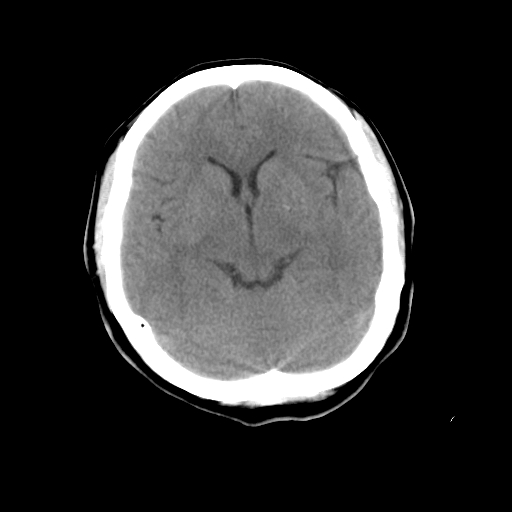

标题: CT23995:女,42岁,前额部外伤1小时,伤后头痛。 [打印本页]

女,42岁,前额部外伤1小时,伤后头痛。

头颅ct平扫未见异常

颅脑ct平扫未见异常,必要时复查

未见明显外伤性改变。